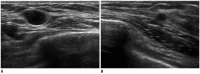

Breast metastases from extramammary malignancies are uncommon. The most common sources are lymphomas/leukemias and melanomas. Some of the less common sources include carcinomas of the lung, ovary, and stomach, and infrequently, carcinoid tumors, hypernephromas, carcinomas of the liver, tonsil, pleura, pancreas, cervix, perineum, endometrium and bladder. Breast metastases from extramammary malignancies have both hematogenous and lymphatic routes. According to their routes, there are common radiological features of metastatic diseases of the breast, but the features are not specific for metastases. Typical ultrasound (US) features of hematogenous metastases include single or multiple, round to oval shaped, well-circumscribed hypoechoic masses without spiculations, calcifications, or architectural distortion; these masses are commonly located superficially in subcutaneous tissue or immediately adjacent to the breast parenchyma that is relatively rich in blood supply. Typical US features of lymphatic breast metastases include diffusely and heterogeneously increased echogenicities in subcutaneous fat and glandular tissue and a thick trabecular pattern with secondary skin thickening, lymphedema, and lymph node enlargement. However, lesions show variable US features in some cases, and differentiation of these lesions from primary breast cancer or from benign lesions is difficult. In this review, we demonstrate various US appearances of breast metastases from extramammary malignancies as typical and atypical features, based on the results of US and other imaging studies performed at our institution. Awareness of the typical and atypical imaging features of these lesions may be helpful to diagnose metastatic lesions of the breast.